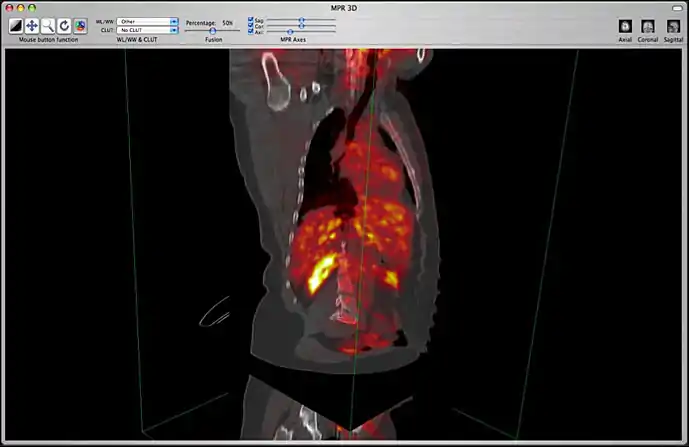

Image fusion is also available for 2D and 3D reconstructions implying that you can use image fusion along with MPR, Volume rendering, etc...

Image fusion in the 3D MPR window